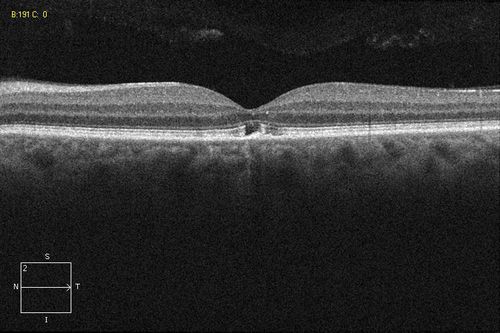

Solar Retinopathy

Foveal defect due to sun staring

Solar Retinopathy - Sun Gazing - OCT

Solar retinopathy, foveal defect

Retina Associates of Western New York

Zeiss Cirrus